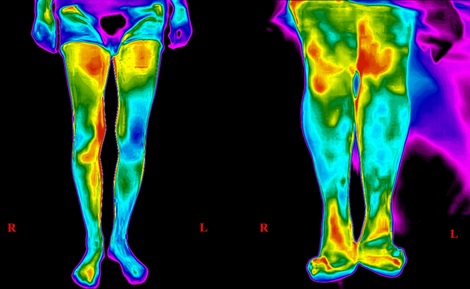

Проф. Иво Петров с обучения за лекари за кардиопулмонална ресусцитация и за термография на 1 юни 2023 г.

Те са в рамките на медицинския форум ЗА ЗДРАВО И МЛАДО СЪРЦЕ в зала "Панорама" на Интер Експо Център с начален час 13:00ч.